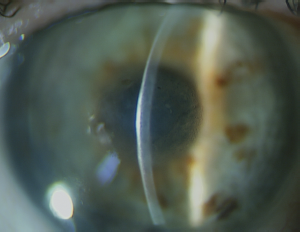

On April 18, 2017, the patient underwent central DR with a diameter of 5.0 mm, and the condition of the cornea in the right eye after 2 days is shown in Figure 3. The uncorrected visual acuity of the right eye was 0.3, and the IOP was 10 mmHg (as measured using the Icare tonometer). Excessive edema and folds in the deep stroma were observed as well as multiple epithelial bullae in the optical zone and transparent corneal periphery with a well-defined endothelial pattern. The margin of DR could not be visualized, although the deeper parts remained unchanged. The patient was examined every week (Figure 4), and after 2 weeks post DR, she underwent accelerated CCL (intensity: 9 W/cm2, 10 min exposure). Two weeks after CCL, the uncorrected visual acuity was 0.3, and the CCT was 546 µm. Stromal edema and the number of bullae were reduced, and the margin of DR was visualized (Fi gures 5 and 6). One month after CCL, the uncorrected visual acuity increased to 0.5 (Figure 7 shows the cornea), and a confocal microscopic examination revealed single ECs in the area of DR (Figure 8). The complete restoration of corneal transparency occurred 4.5 months after surgery, with the uncorrected visual acuity reaching 1.0, CCT of 553 µm, and ECD of 1546 cells/mm2 (Figures 9–11).

Fig. 3. Cornea after descemetorhexis

Fig. 4. Cornea 2 weeks after CXL

Fig. 5. Cornea (arrows indicate the border of the descemetorhexis)

Fig. 6. Anterior segment optical coherence tomography (arrows indicate the border of the descemetorhexis)

Fig. 7. Cornea (arrows indicate the border of the descemetorhexis)